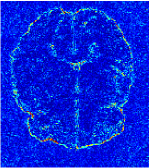

All the experiments are implemented on a Windows workstation with Intel Core i9 CPU at 3.3GHz and an Nvidia GTX-1080Ti GPU with 11GB of graphics card memory via TensorFlow Abadi et al. (2016). The parameters in the proposed network are initialized by using Xavier initialization Glorot and Bengio (2010). We trained the meta-learning network with four tasks synergistically associated with four different CS ratios: 10%, 20%, 30%, and 40%, and test the well-trained model on the testing dataset with the same masks of these four ratios. We have 300 training data for each CS ratio, which amount to total of 1200 images in the training dataset. The results for and MR reconstructions are shown in Tables 5.4 and 5.4 respectively. The associated reconstructed images are displayed in Figures 1 and 3. We also test the well-trained meta-learning model on unseen tasks with radio masks for skewed ratios: 15%, 25%, 35%, and random Cartesian masks with ratios 10%, 20%, 30% and 40%. The task-specific parameter for the unseen tasks are retrained for different masks with different sampling ratios individually with fixed task-invariant parameters . In this experiments, we only need to learn for three skewed CS ratios with radio mask and four regular CS ratios with Cartesian masks. The experimental training proceed on less data and iterations, where we performed on 100 MR images with 50 epochs. For example, for reconstructing MR images with CS ratio 15% radio mask, we fix the parameter and retrain the task-specific parameter on 100 raw data with 50 epochs, then test with renewed on our testing data set with raw measurement that sampled from radio mask with CS ratio 15%. The results associated with radio masks are shown in Table 5.4 and 5.4, Figure 2 and 4 for and images respectively. The results associated with Cartesian masks are list in Table 5.4 and reconstructed images are displayed in Figure 5.

Qualitative comparison between conventional and Meta-learning methods are shown in Figure 1 and 3, which display the reconstructed MR images of the same slice for T1 and T2 respectively, we label the zoomed-in details of HGG in the red boxes. We observe the evidence that conventional learning is more blurry and lost sharp edges, especially in lower CS ratios. From the point-wise error map, we find meta-learning has the ability to reduce noises especially in some detailed and complicated regions comparing to conventional learning.